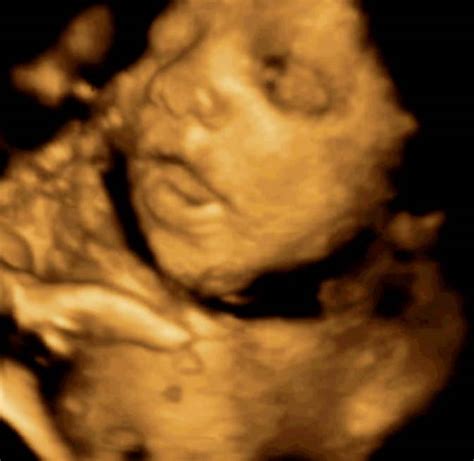

5. Mesec nosečnosti (18. do 21. teden):V sedemnajstem tednu plod je velikosti hruške, dolg 14.5 cm in tehta 110 g. Ušesa so popolnoma formirana, razvija se sluh. Začne se kopičiti maščevje. V osamnajstem tednu plod je dolg 13 cm in tehta 140 g. Srček je popolnoma formiran, plod sliši srčni utrip mame in zvoke iz okolice. V devetnajstem tednu plod je velikosti manga, dolg 17.8 cm in tehta 200 g. Razvija se verniks (beli, mastni premaz), ki ščiti plod. Vsa čutila se intenzivno razvijajo. Lahko se pojavi bolečina krožne vezi, ki podpira maternico. V dvajsetem tednu plod je velikosti banane, dolg 19.7 cm in tehta 260 g. Notranji organi so na svojem mestu. Polovica nosečnosti je mimo, velikost maternice je do popka. Pri okoli 20. tednu se opravi obširnejši ultrazvok, morfologija, kjer ginekolog pregleda razvoj posteljice in otroka. Vidijo se premiki, sliši se bitje srca, pogosto se izve tudi spol otroka.